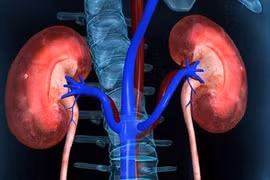

Tổn thương thận cấp diễn biến phức tạp, có tỷ lệ tử vong lên đến 50% từ những biểu hiện tưởng chừng đơn giản như thiểu niệu hoặc vô niệu, phù tay chân, mệt mỏi, buồn nôn...